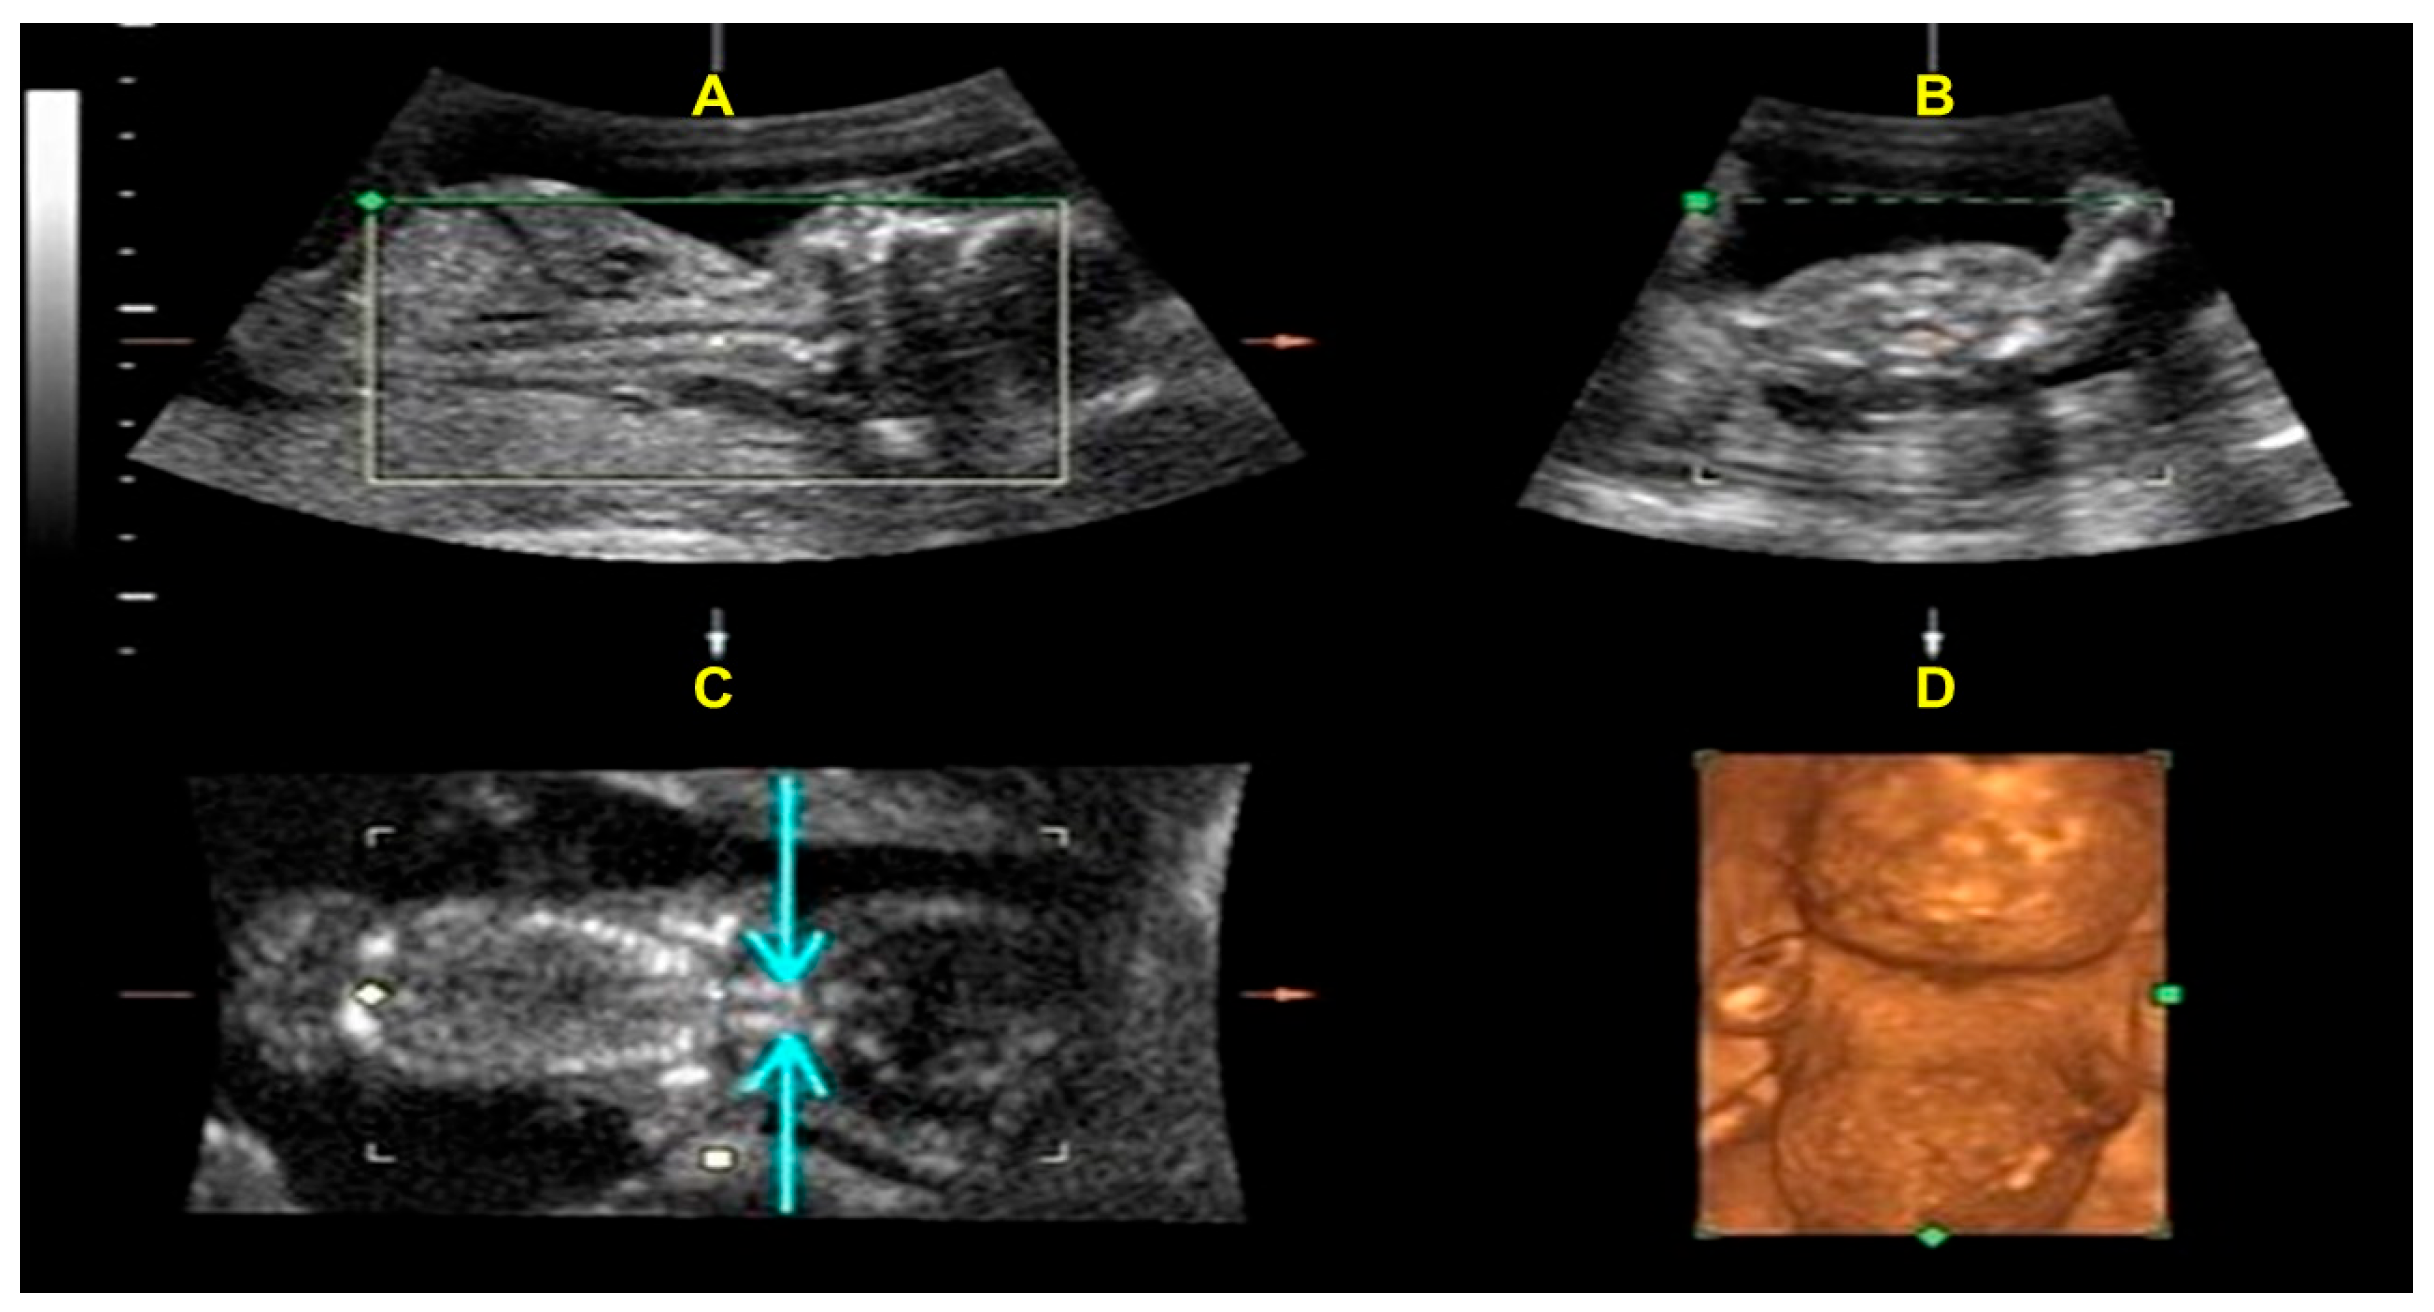

2. Case Presentation